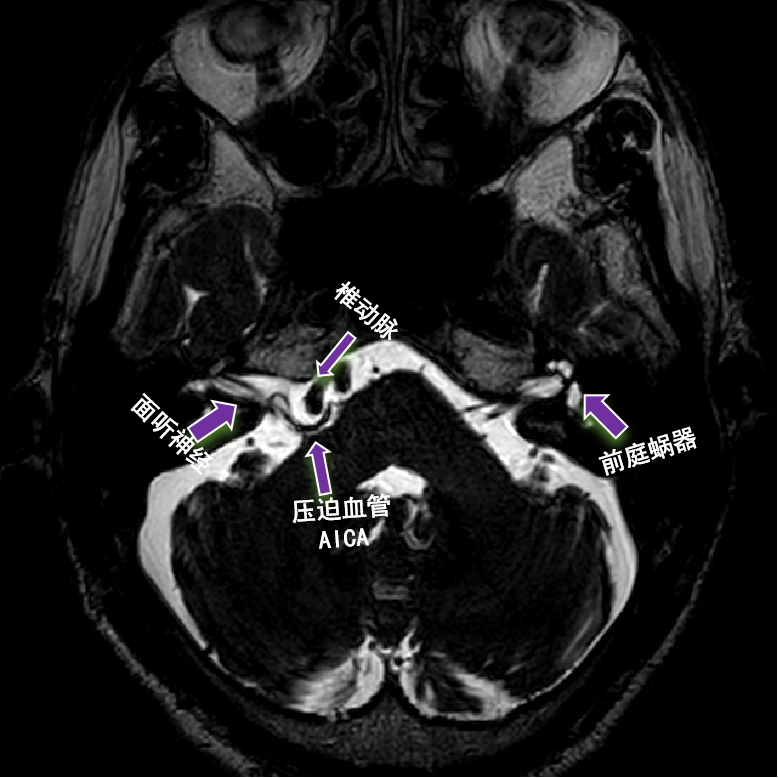

右眼皮跳3年 原来是面肌痉挛!

眩晕挂啥科?清华长庚开设眩晕专病中心